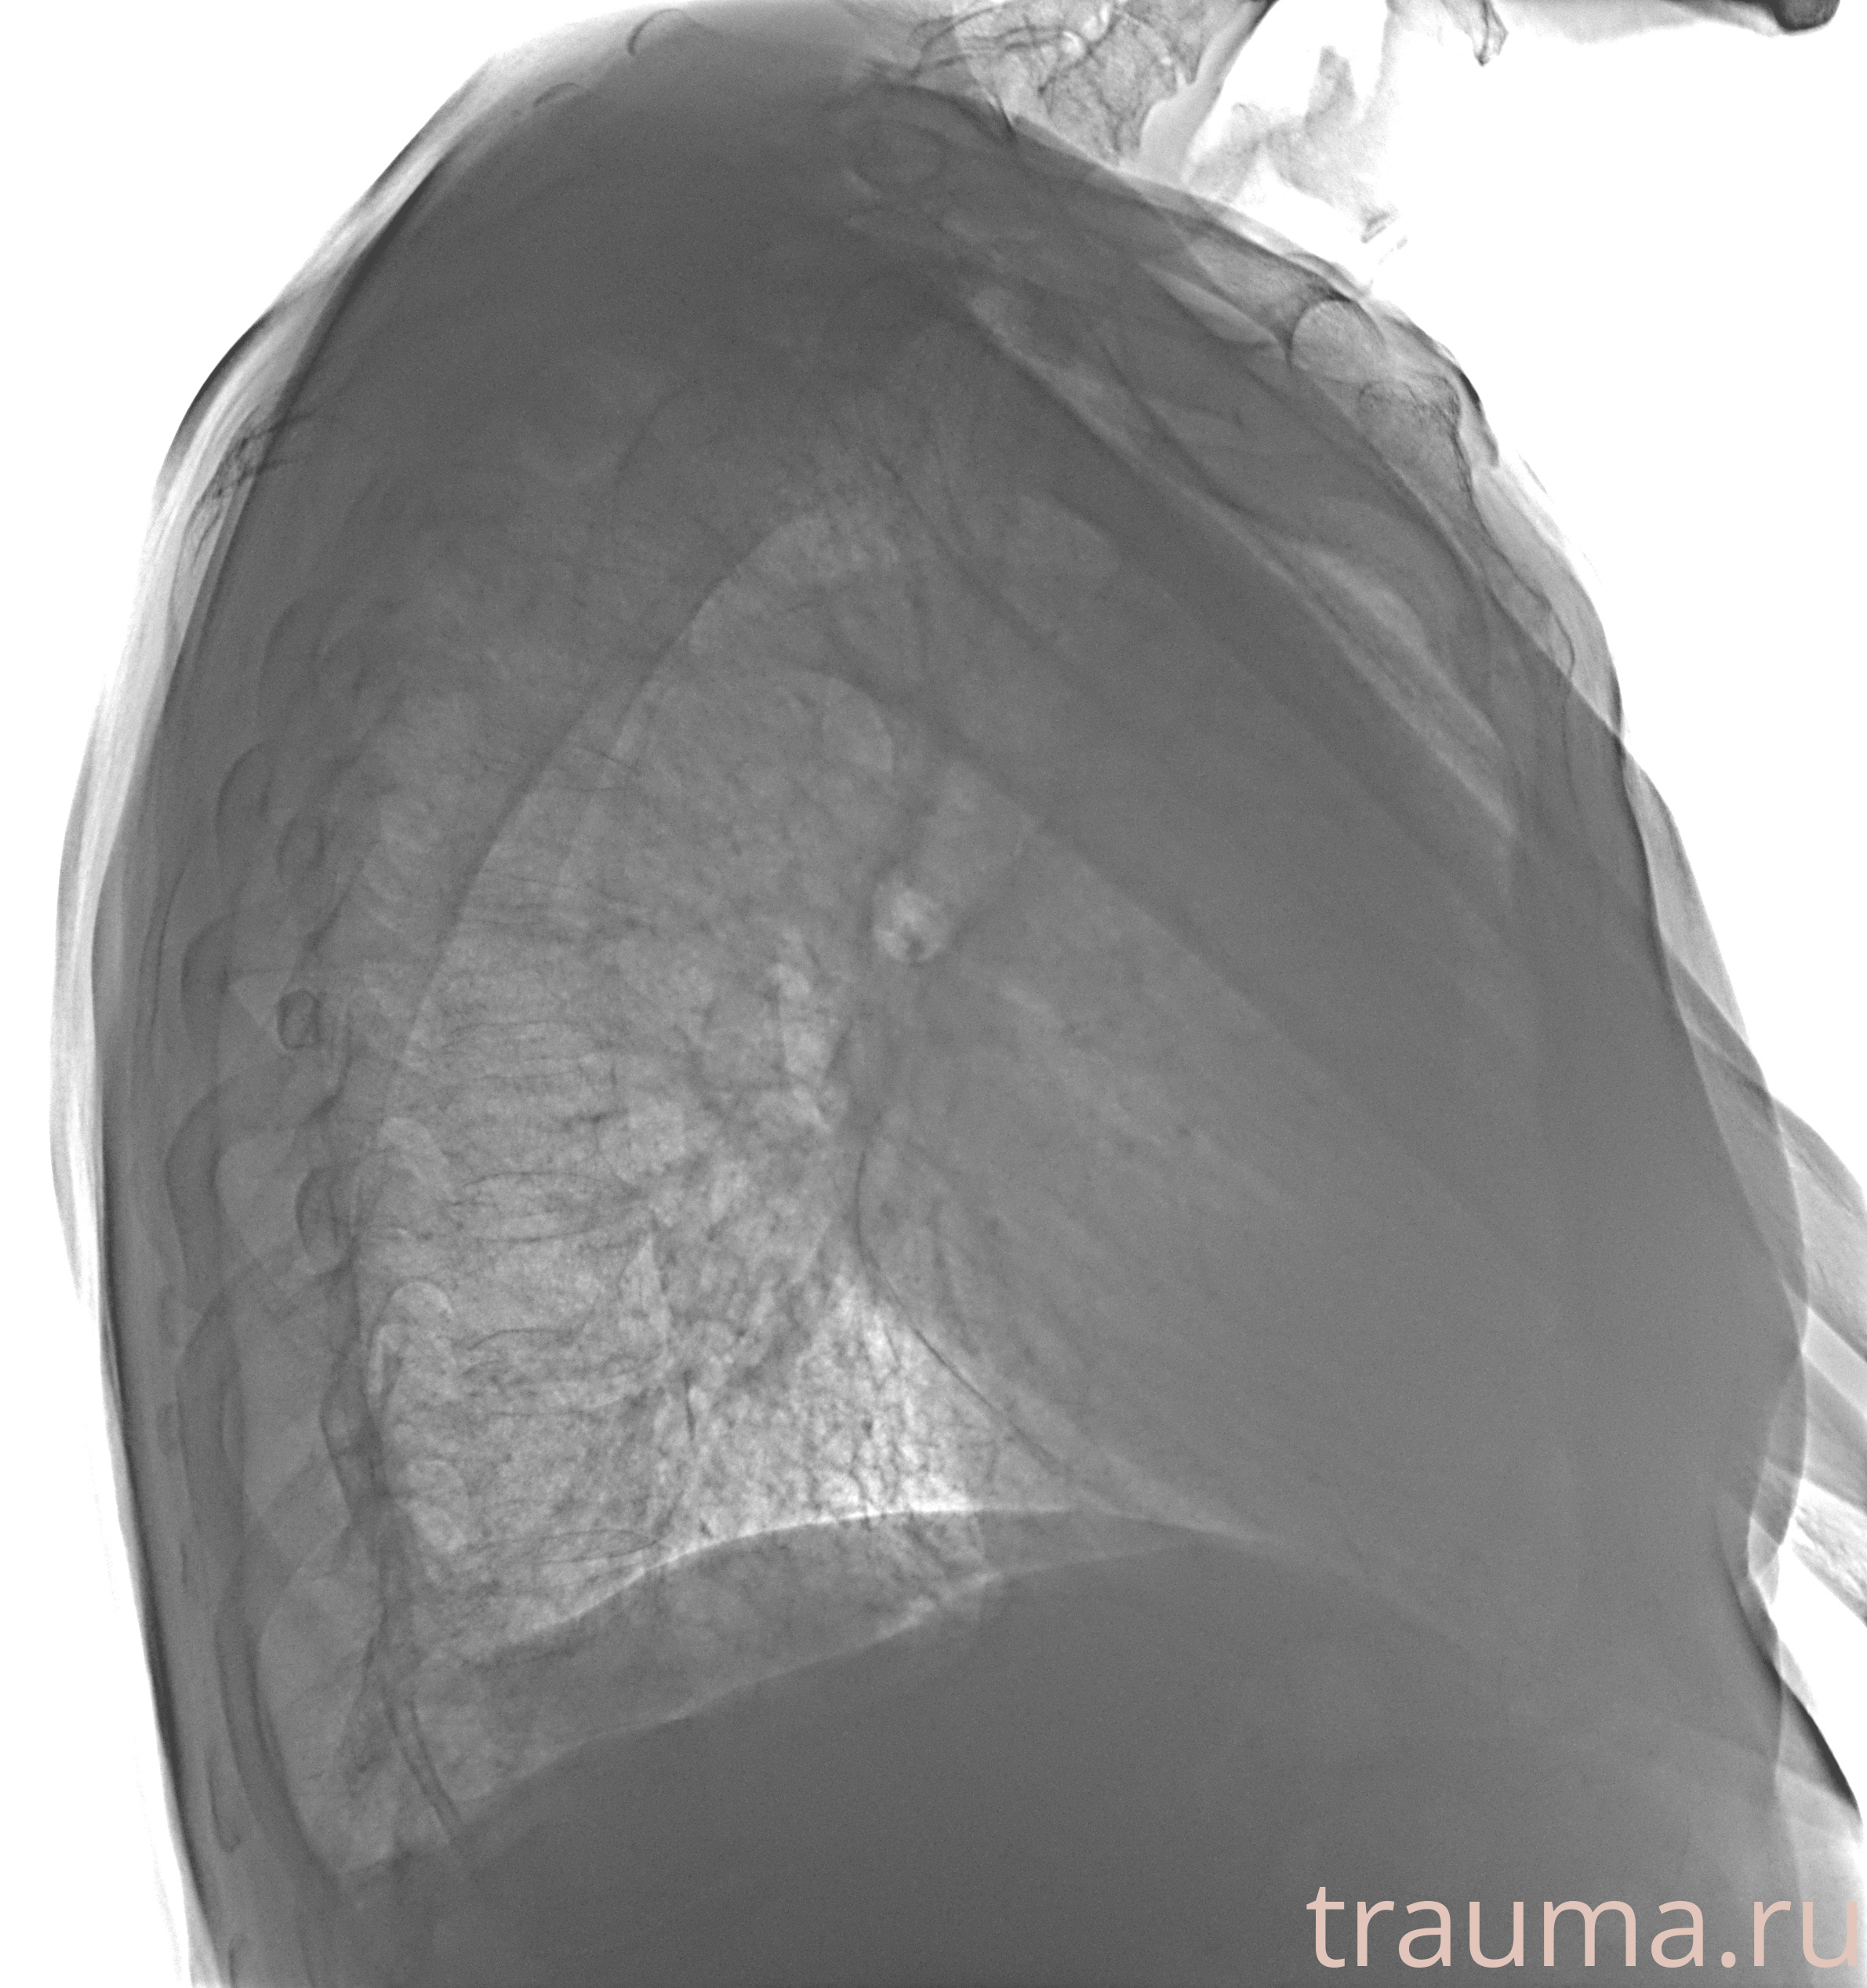

Рентген на дому: по вашему адресу приезжает врач-рентгенолог, травматолог-ортопед с мобильным рентгеновским аппаратом, проводит диагностику травмы или заболевания, делает необходимые рентгенограммы, дает рекомендации по дальнейшему лечению. Получить качественные снимки в домашних условиях возможно благодаря уникальной методике, разработанной МосРентген Центром для института  Склифосовского